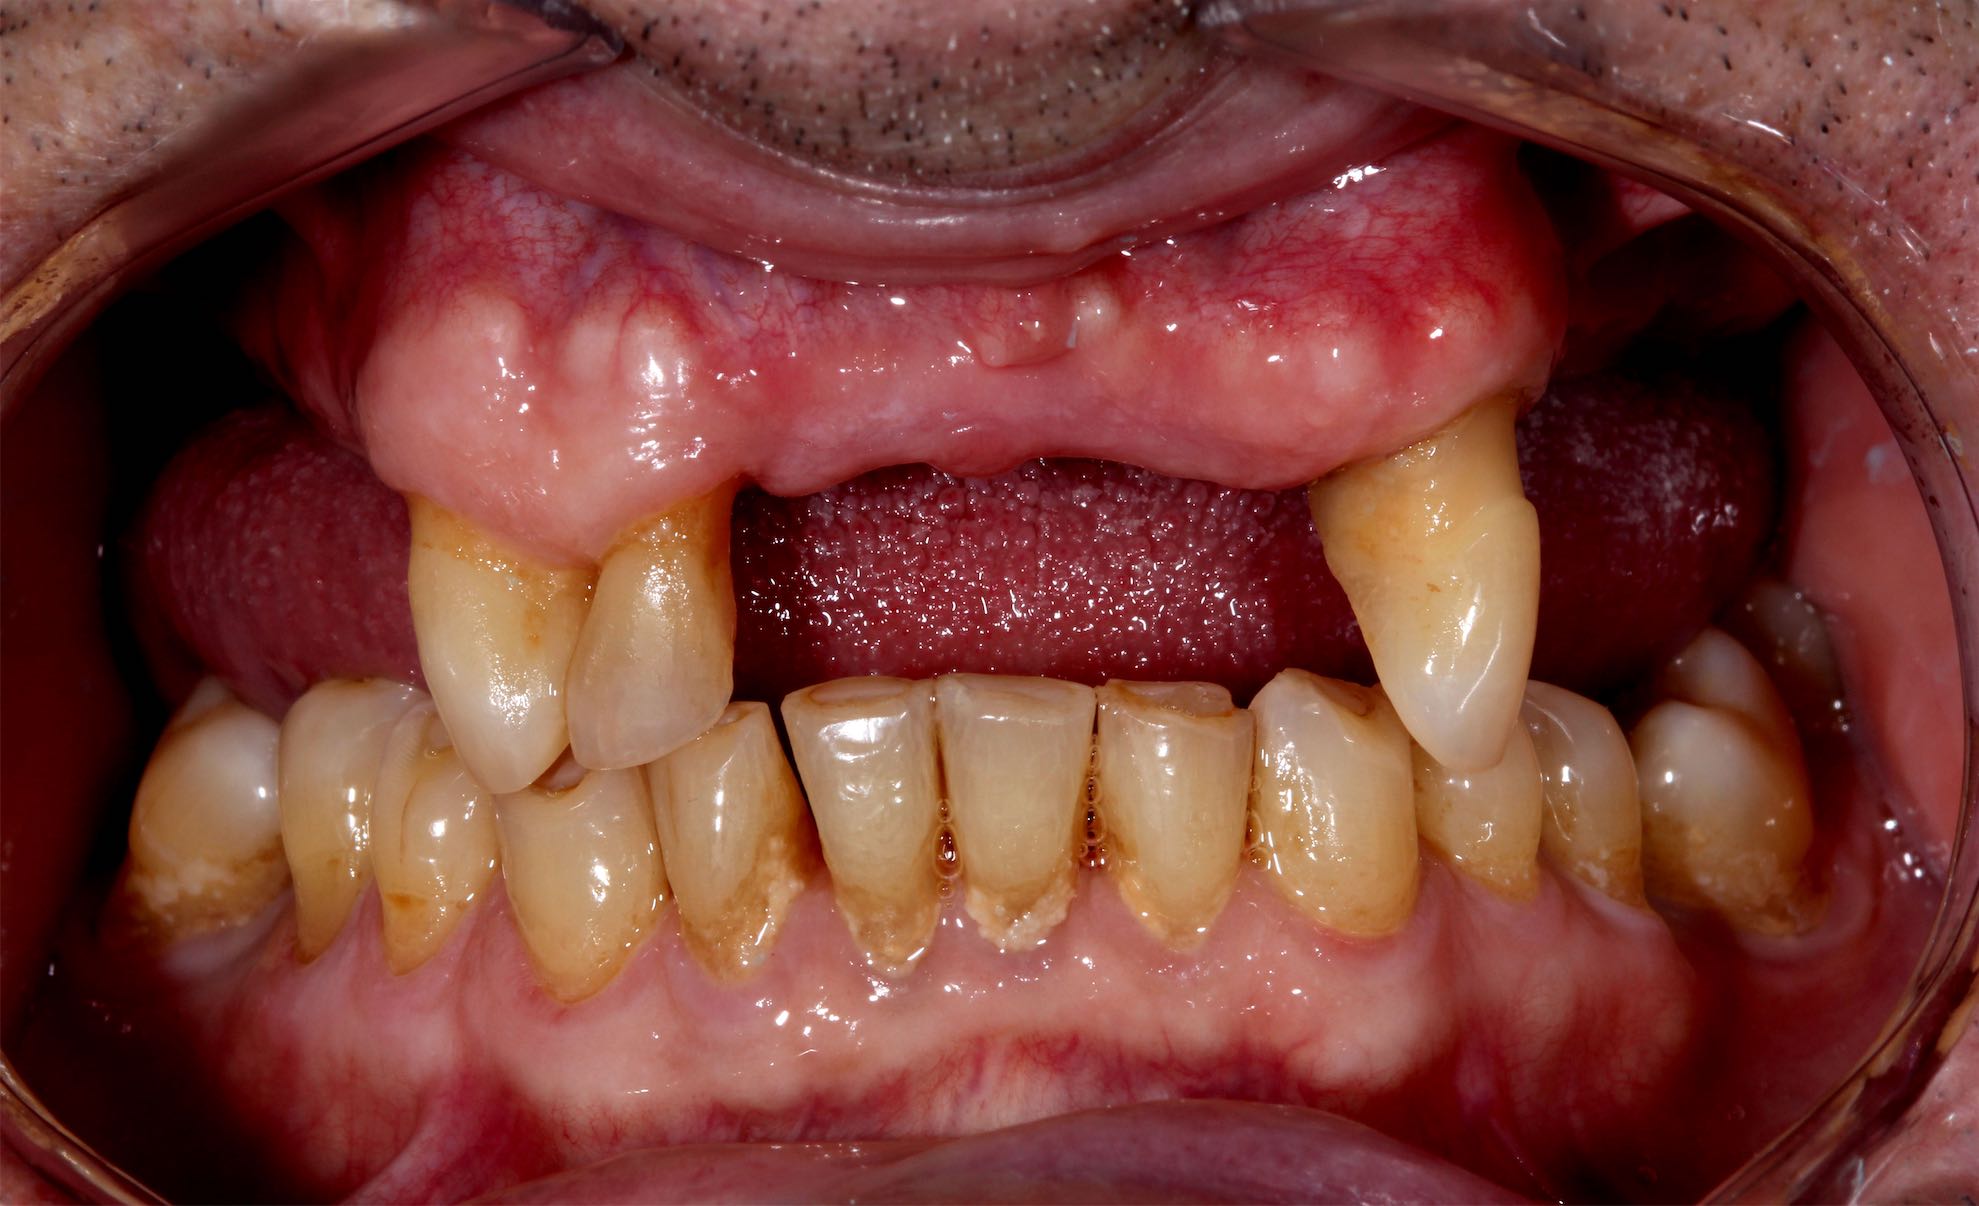

Caso de Rehabilitación completa y aumento de DV

BeforeAfter